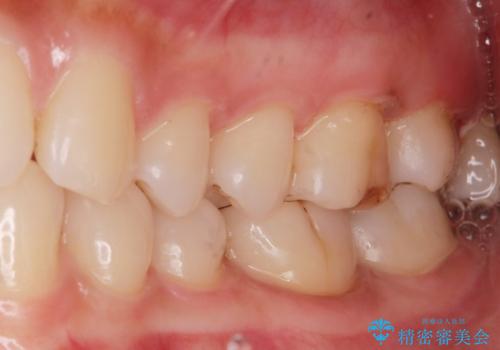

着色が気になる(エアフロー)

- 着色が気になるとの事で来院。

エアフローでしっかり着色を取り除きました。

着色が目立たなくなり大変満足して頂けました。